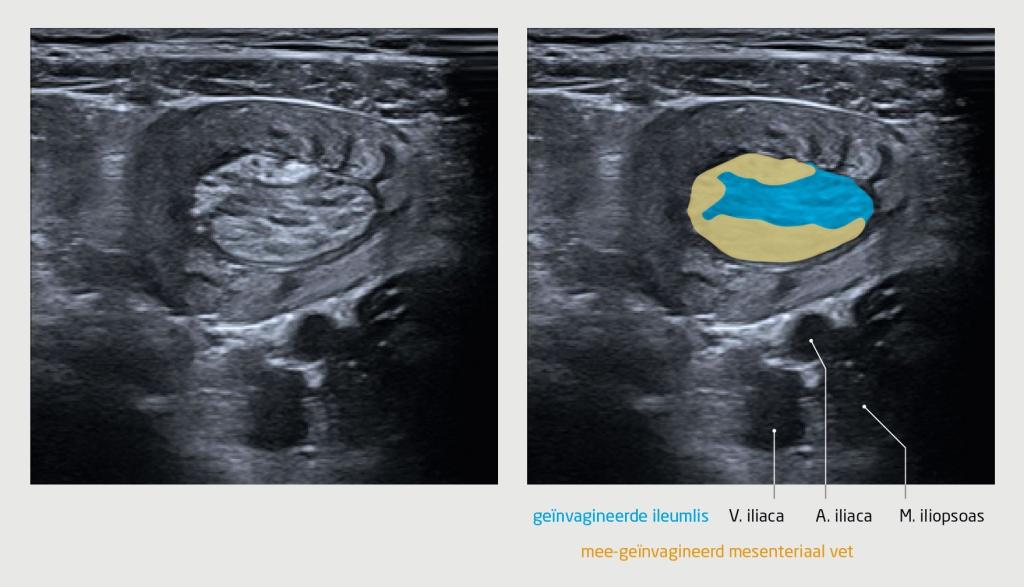

In de verklarende tekening bij figuur 2 waren de V. iliaca, A. iliaca en M. iliopsoas per abuis aangeduid als vergrote mesenteriale lymfeklieren. De verklarende tekening en het bijschrift zijn aangepast.

Figuur 2

Echografisch beeld van het abdomen van patiënt A. Er is een invaginatie te zien, waarbij een ileumlis geïnvagineerd is in een andere darmlis. De geïnvagineerde lis is wat schuin aangesneden en is asymmetrisch omgeven door mee-geïnvagineerd mesenteriaal vet. De forse wandverdikking en de ruimte-innemende werking ervan op de buikwand bij compressie geven aan dat het hier vermoedelijk niet gaat om een onschuldige, spontane ileo-ileale invaginatie. Met dank aan dr. J. Puylaert en dr. W. Klein, (kinder)radiologen.